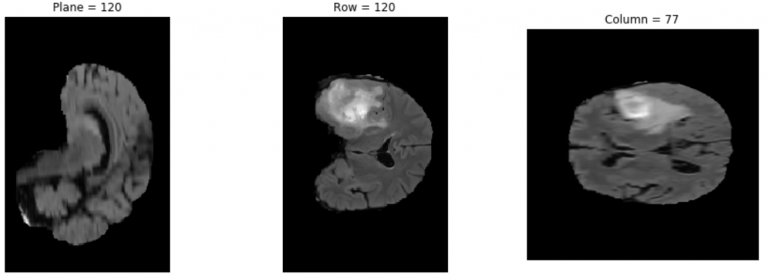

예측 결과 플로팅

다음의 코드 예제에서는 \results 폴더에서 선택한 결과의 하나를 플로팅합니다.

data= np.load('/results/vol_0.npy')

(n_plane, n_row, n_col) = data.shape

_, (a, b, c) = plt.subplots(ncols=3, figsize=(15, 5))

show_plane(a, data[n_plane // 2], title=f'Plane = {n_plane // 2}')

show_plane(b, data[:, n_row // 2, :], title=f'Row = {n_row // 2}')

show_plane(c, data[:, :, n_col // 2], title=f'Column = {n_col // 2}')